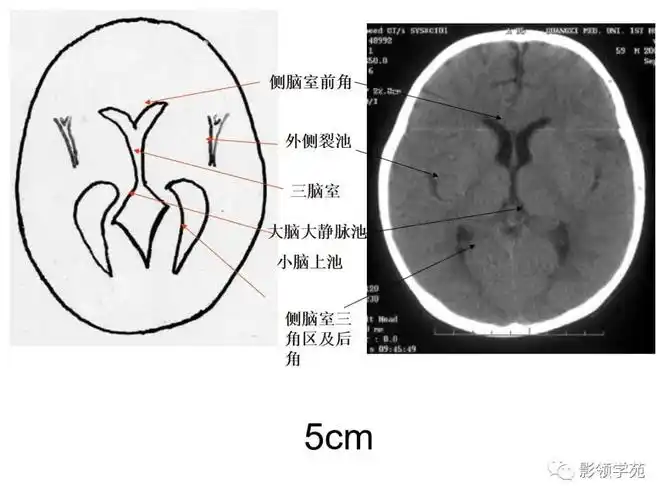

基底节区结构基底节(basal ganglia)(又称基底神经节)是指从胚胎端脑